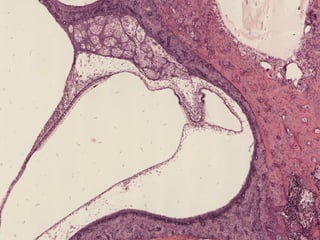

Canal Vestibular

Conducto Coclear

Membrana Basilar

Escala Vestibular

Escala Timpánica

Membrana Vestibular

Órgano de

Corti

Órgano de Corti

Membrana Tectorial

Ganglio Espiral

Ligamento Espiral